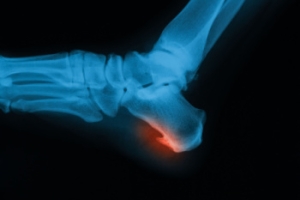

Heel Spurs and Their Classifications

A heel spur is a bony growth that forms on the heel bone, often linked to physical stress, inflammation, or plantar fasciitis. Heel spurs can be classified into four types, including absent, indicating no visible spur. Horizontal spurs grow straight across the heel, vertical spurs point upward, while hooked spurs curve toward surrounding tissues, often causing more discomfort. Symptoms include heel pain, tenderness, and swelling, especially during walking or standing. Causes include repetitive strain, poor footwear, obesity, and high impact activities. A podiatrist can diagnose the type of heel spur, provide targeted treatments, and recommend supportive footwear or orthotics. If you have heel pain, it is suggested that you consult a podiatrist who can provide an accurate diagnosis and treatment.

Heel spurs are formed by calcium deposits on the back of the foot where the heel is. This can also be caused by small fragments of bone breaking off one section of the foot, attaching onto the back of the foot. Heel spurs can also be bone growth on the back of the foot and may grow in the direction of the arch of the foot.

Older individuals usually suffer from heel spurs and pain sometimes intensifies with age. One of the main condition's spurs are related to is plantar fasciitis.

Pain

The pain associated with spurs is often because of weight placed on the feet. When someone is walking, their entire weight is concentrated on the feet. Bone spurs then have the tendency to affect other bones and tissues around the foot. As the pain continues, the feet will become tender and sensitive over time.

Heel Spurs

Heel spurs are the result of calcium deposits that cause bony protrusions on the underside of the heel. Heel spurs are usually painless, but they have the potential to cause heel pain. Heel spurs tend to be associated with plantar fasciitis, which is a condition that causes inflammation of the band of connective tissue that runs along the bottom of the foot. They most often occur to athletes whose sports involve a lot of running and jumping.

Some risk factors for developing heel spurs include running and jogging on hard surfaces, being obese, wearing poorly fitting shoes, or having walking gait abnormalities.

It is possible to have a heel spur without showing signs of any symptoms. However, if inflammation develops at the point of the spur’s formation, you may have pain while walking or running. In terms of diagnosis, sometimes all a doctor needs to know is that the patient is experiencing a sharp pain localized to the heel to diagnose a heel spur. Other times, an x-ray may be needed to confirm the presence of a heel spur.

Heel spurs can be prevented by wearing well-fitting shoes that have shock-absorbent soles. You should also be sure that you are choosing the right shoe for the activity you want to partake in; for example, do not wear walking shoes when you want to go on a run. Additionally, maintaining a healthy weight can be beneficial toward preventing heel spurs, as it will prevent an excess amount of pressure being placed on the ligaments.

There are a variety of treatment options for people with heel spurs. Some of these include stretching exercises, physical therapy, shoe inserts, or taping and strapping to rest stressed muscles and tendons. If you have heel pain that lasts longer than a month, don’t hesitate to seek help from a podiatrist. Your doctor can help you determine which treatment option is best for you.